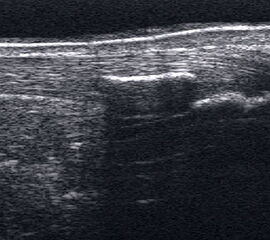

Fibulafraktur mit Unterbrechung der Kortikalis und Hämatom.

Abbildung 13

Lagerung: Rückenlage, leichte Innrotation des Fußes.

Schnittebene: LS über distaler Fibula.

Referenzstruktur: Fibula im Längsverlauf.

Befunde: Bei einer Außenknöchelfraktur ist eine Unterbrechung der echogenen metaphysären Knochenlinie mit umgebendem flachen, echoarmen periostalen Hämatom zu sehen (Abb.13).

Cave: Ein Os subfibulare kann ebenfalls fälschlicherweise als Fibulaverletzung interpretiert werden!